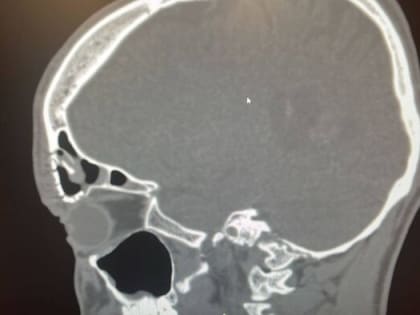

Оренбургские врачи заменили часть раздробленного черепа титановой платиной

Врачи ЛОР-отделения Оренбургской областной клинической больницы им. В.И. Войнова успешно провели сложную операцию на передней стенке лобной пазухи.